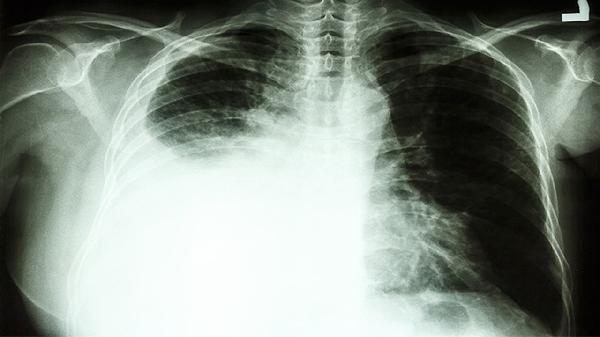

2、非小细胞肺癌

对于中晚期非小细胞肺癌患者,复方斑蝥胶囊可协同吉非替尼等靶向药物增强抗癌效果。其活性成分能诱导肿瘤细胞凋亡,抑制血管生成,缓解咳嗽、胸痛等症状。建议联合放疗使用,定期复查胸部CT评估疗效。